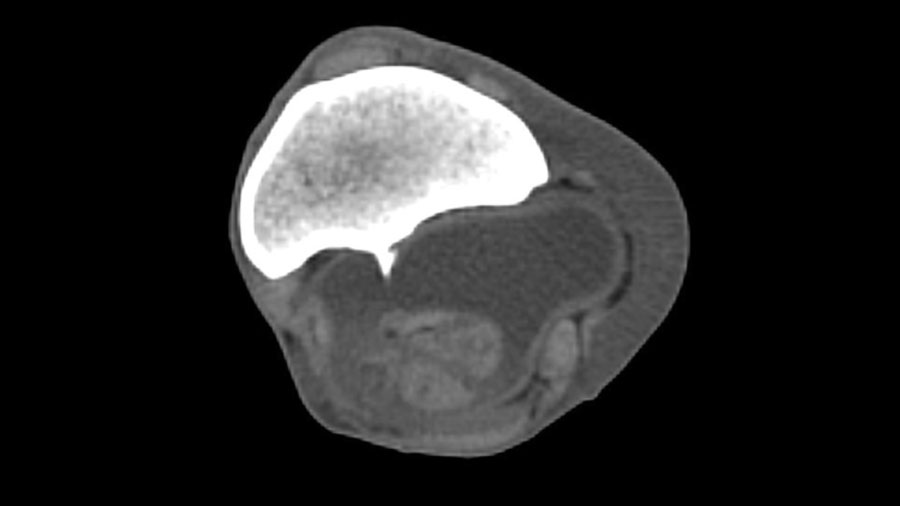

Computed tomography

Computed tomography (CT) provides the greatest diagnostic accuracy. CT reconstruction clearly demonstrates the position of the spike, the presence of synovial effusion, and any associated tendon damage. Flexed, non‑weightbearing images may allow tears in the epitenon to open when not under tension, while seeing the spike protruding into the body of the DDFT on a weightbearing image is diagnostic. When available, CT with intra‑thecal contrast is ideal, particularly for surgical planning.

In many cases, CT also helps clarify the extent of tendon involvement, especially when conventional imaging has been inconclusive.

Damage to the DDFT may also be apparent, particularly with flexed, non-weightbearing images allowing tears in the epitenon to open when not under tension. Seeing the spike protruding into the body of the DDFT on a weightbearing image is diagnostic.

If available, CT of the carpal sheath, ideally with intra-thecal contrast, will provide the most accurate diagnostic information, helping guide surgical planning as well as predicting prognosis in the presence of concurrent injury to the region.